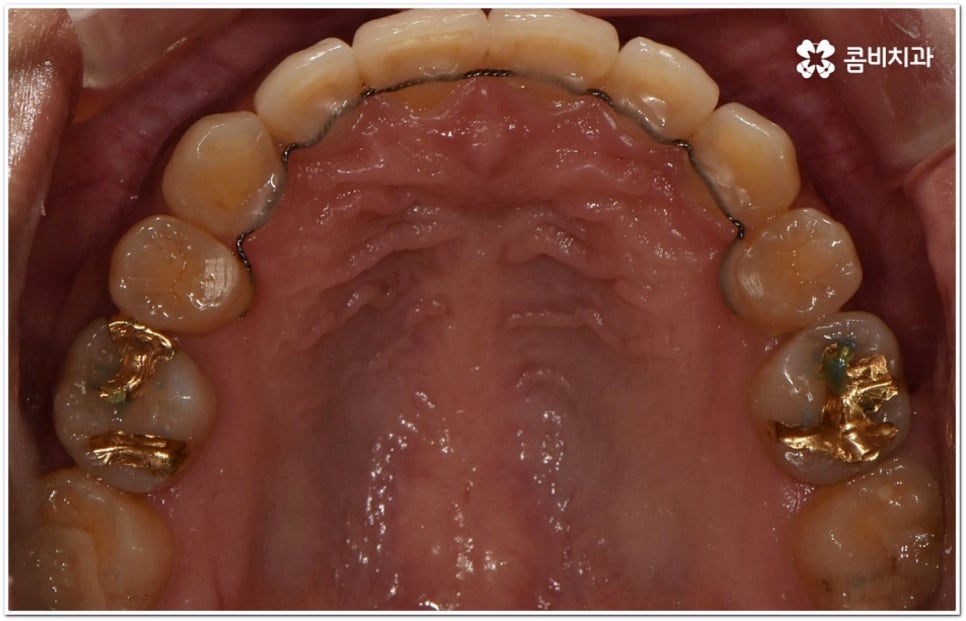

환자마다 치열, 교합, 치아가 튀어나온 각도, 잇몸이 드러나는 정도, 상악과 하악의 구조 및 관계 등 턱관절 관련 부분 상황이 모두 다르기 때문에 3D CT 같은 정밀 검진 기계를 통해 이를 꼼꼼하게 살펴보고 각각에 맞는 계획을 세밀하게 세워 교정 치료를 진행해 줄 필요가 있어요. 이때 환자분들의 상황에 따라 양악수술과 같은 외과적인 방법을 병행해야 하는 케이스도 있을 수 있기 때문에 돌출입을 가지고 계신 분들 중에서 수술에 부담을 느끼고 지레 치료를 포기하신 분들도 있을 수 있는데 정도가 많이 심각하지 않고 구조적인 원인이 크지 않다면 대부분의 케이스는 치아교정 만으로도 충분히 개선이 가능하니 먼저 돌출입교정치과 에 들러서 정밀 검사를 진행한 후 치료 방향에 대해 의료진과 논의해 보시면 좋을 거예요.

말씀드렸던 것처럼 돌출입의 원인이 치아 만의 문제, 즉 각도가 살짝 앞으로 뻐드러진 데 있고 상태가 그다지 심한 것 같지 않다면 보다 빠르고 간편한 수복이 가능할 수 있어요. 튀어나온 부분을 집어넣기 위해서는 발치가 필수적이지 않을까 생각하실 수 있는데 후방으로 이동시켜 줄 공간이 충분하다면 치간 삭제, 악궁 확장, 어금니 후방 이동 등 다른 방법을 이용하여 비발치 치료 과정을 진행할 수 있으므로 너무 걱정하지 않으셔도 될 거예요. 오히려 환자분들의 다양한 상황을 고려하지 않고 무리하게 발치 교정을 진행하게 되면 옥니나 합죽이와 같은 부작용이 일어날 수도 있기 때문에 원인을 정확하게 파악하고 적절한 치료를 할 수 있도록 임상 경험이 풍부하고 뛰어난 노하우를 가지고 있는 숙련된 의료진에게 교정 치료를 맡기시는 것이 굉장히 중요하다고 할 수 있습니다.